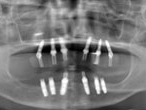

レントゲン

上顎のオールオン4によるインプラント治療

6本のインプラント埋入によるオールオンフォー手術で確実な初期固定が得られたため、手術当日にフルブリッジ(仮歯)をインプラントにしっかり固定して治療を終えました。その結果、手術当日から食事もできるまでに咬合機能が回復して、患者さんにとても満足していただいた症例です。